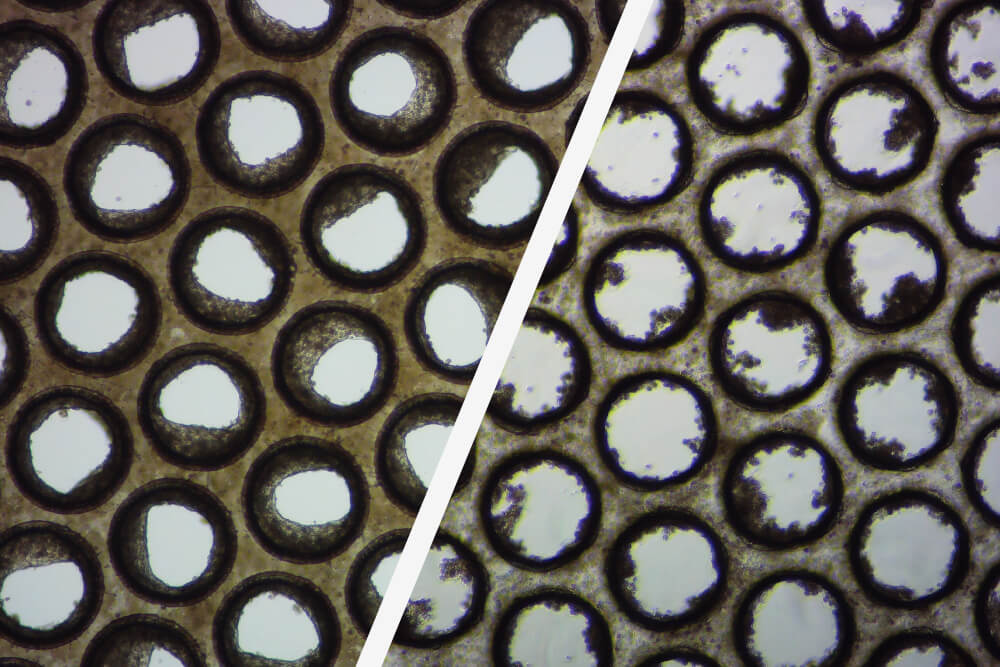

图1-不同来源捐赠者的肝微组织

由于 OOC(也称为微生理系统 (MPS))的目的是尽可能地重现人类生理学,因此我们有目的地选择使用原代人类细胞,但是,即使您严格遵循解冻/接种方案,也不意味着您的细胞在 3D OOC 培养中表现良好(图1、图2)。

图2-良好/较差的肝脏微组织